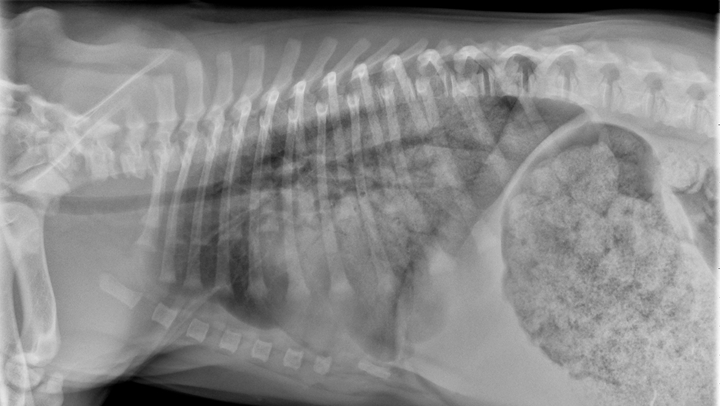

驗血的結果可能偶而會出現血液中的嗜酸性球比例增加。X光下也會出現廣泛性的肺部支氣管浸潤的影像。通常這類疾病需要透過支氣管內視鏡導引的支氣管肺泡灌洗檢查,採檢出呼吸道內的黏液去分析是否包含了大量的嗜酸性球。